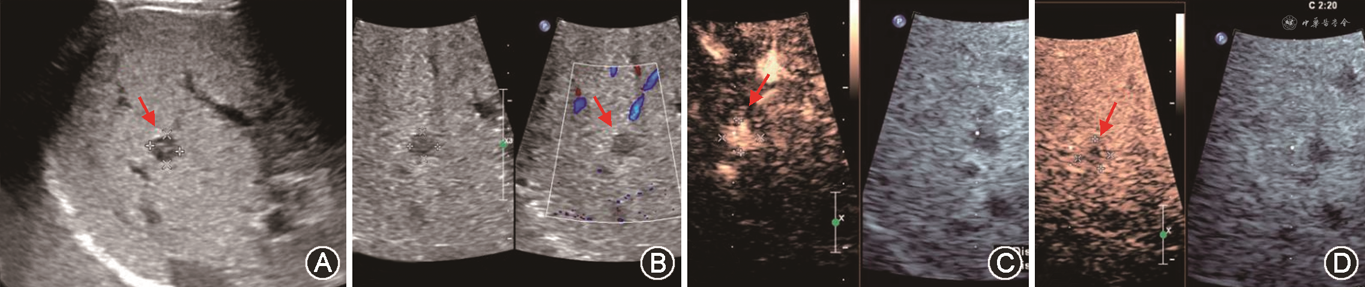

(1)PVT:PVT多发生于肝外门静脉段或门静脉吻合口。肝移植前受体有PVT病史、门静脉内径较细(<5 mm)、患者处于高凝状态及有脾切除手术病史等是好发因素[47,51,71]。移植肝PVT声像图表现为门静脉管腔内见实质回声,CDFI显示血流充盈缺损或不能测及彩色血流。急性PVT灰阶超声上有时可呈无回声表现,需结合CDFI检查进行鉴别。当CDFI检查门静脉血流显示不清时,应用超声造影可以改善门静脉的显示,明确门静脉是否闭塞(图17)[33,72]。